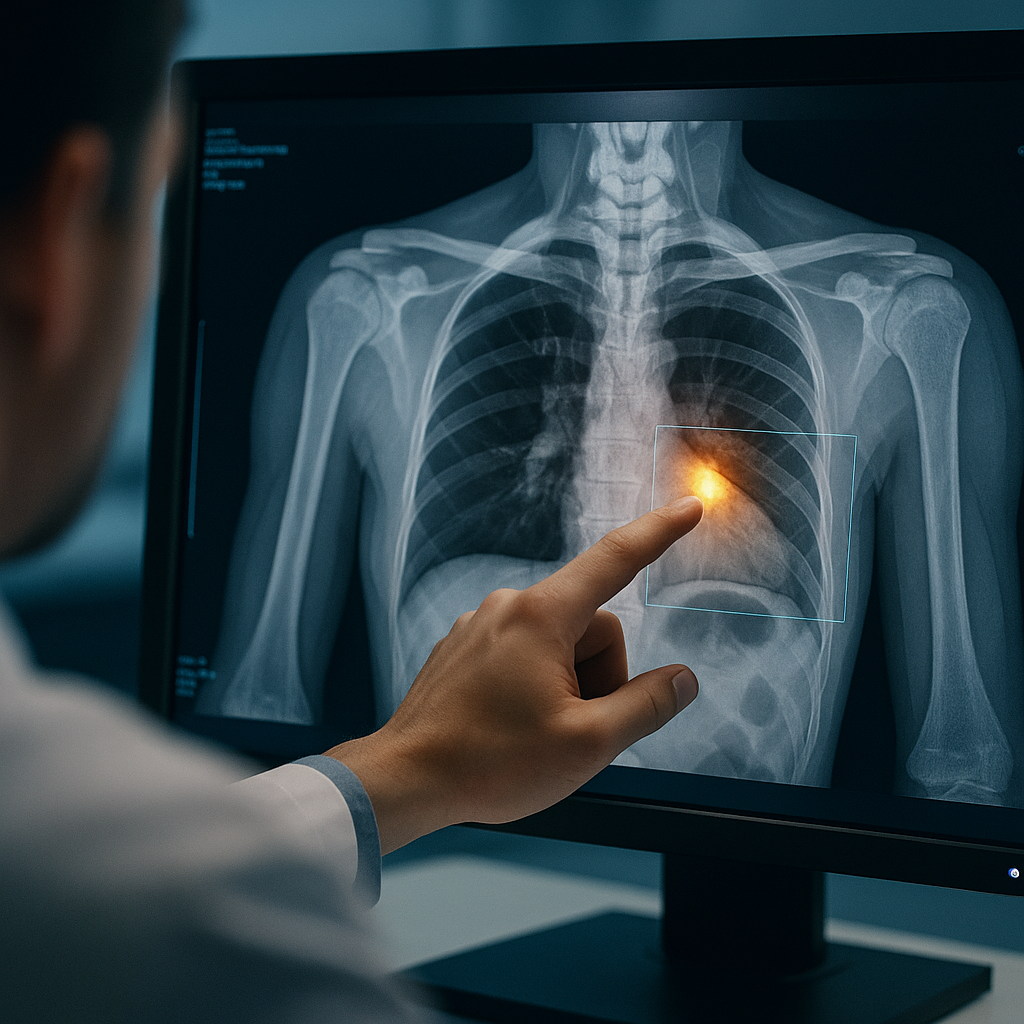

Prologue: The Case That AI Caught — and a Doctor Saved

It was a rainy Tuesday evening at a busy tertiary hospital in Mumbai. The emergency department was overflowing with patients — accidents on the Western Express Highway, fever cases from monsoon outbreaks, elderly patients with cardiac discomfort. Triage nurses moved swiftly, lab technicians rushed between departments, and the radiology team prepared for yet another long night.

• Among the chaos came a middle-aged man who complained of mild, persistent chest pain. His blood pressure was normal. ECG non-specific. Troponin slightly elevated but inconclusive. The emergency physician wasn’t convinced it was a cardiac event, but something felt unusual.

• The CT scan reached Dr. Rhea, a 33-year-old radiologist who had trained at one of India’s best institutes. She opened the scan. At a glance, nothing alarming stood out.

But then, something flashed.

• The AI triage tool flagged a tiny area — a subtle abnormality near the aortic arch.

Something almost invisible.

Something that could easily be missed at this early stage.

• AI assigned a probability score. It suggested comparison with prior imaging. It highlighted a pattern consistent with early aortic aneurysm.

• Dr. Rhea zoomed in, reviewed, validated, and immediately alerted the cardiac team.

• Within three hours, the patient was undergoing a lifesaving intervention.

• When Dr. Rhea looked back on the case later, she said something that captured the future of radiology in a single sentence:

“AI didn’t make the diagnosis. It reminded me where to look.” This is the radiology revolution.Not AI vs radiologist — but radiologist + AI.